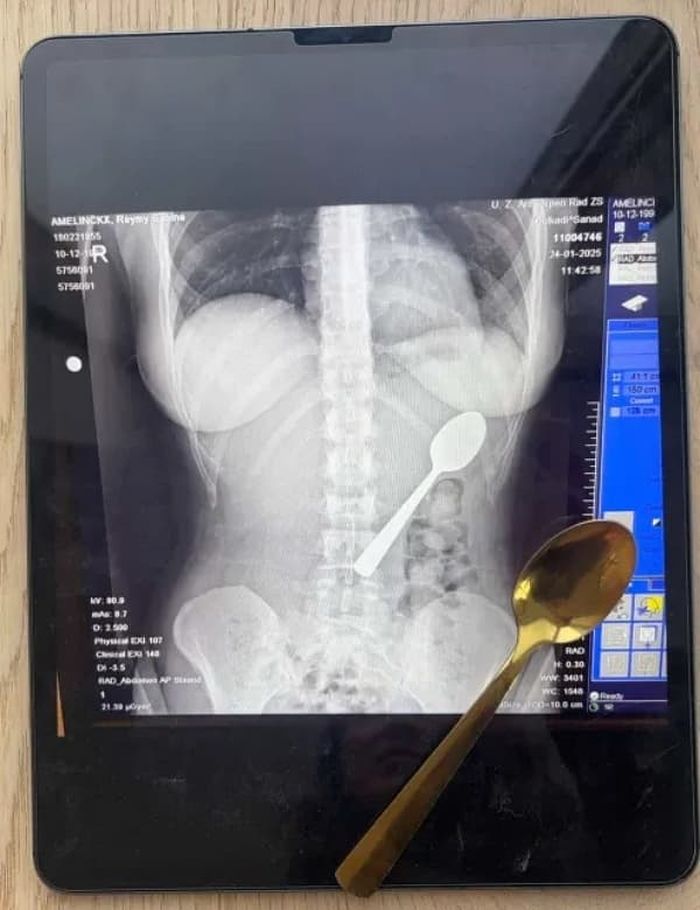

갑자기 달려든 강아지에 놀라 ‘17cm’ 숟가락 삼킨 여성의 엑스레이 사진

요거트를 맛있게 먹고 있던 한 여성이 갑자기 달려든 강아지 때문에 무려 17cm 길이의 숟가락을 통째로 삼켜버린 사건이 발생해 큰 충격을 주고 있습니다.

벨기에에 사는 28세 여성 레이미 아멜링크스(Reymy Amelinckx) 씨는 소파에 앉아 평화롭게 요거트를 먹고 있었습니다.

인터넷을 검색해본 레이미 씨는 상황이 매우 심각하다는 것을 깨닫고 급히 응급실로 향했습니다. 엑스레이를 찍어보니 정말로 기다란 숟가락이 그녀의 위장에 떡하니 자리 잡고 있었죠.

의사들은 숟가락이 너무 커서 자연적으로 배출될 수 없다고 진단했습니다. 이틀 동안 수술을 기다리는 내내 그녀는 갈비뼈 사이로 숟가락이 부딪히는 소름 돋는 느낌을 참아야 했습니다.